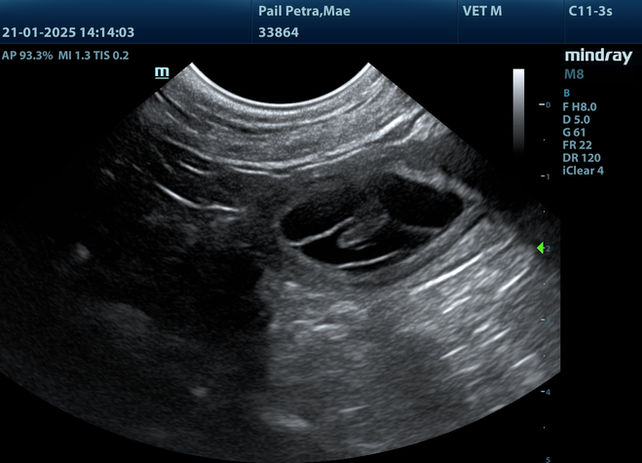

21.01.2025 - Tag 30 - Woche 5:

Juhuu, unsere Mae ist trächtig und hiermit offiziell bestätigt.

Heute hatten wir einen Ultraschalltermin bei unsere Tierärztin. Drei Fruchthöhlen sind klar erkennbar.

Nachdem Mae schon seit ein paar Tagen recht wenig frisst, wenn dann nur das Feuchtfutter und natürlich Leckerli - die gehen immer - habe ich mir schon gedacht, dass sie trächtig ist.

Wir freuen uns riesig.